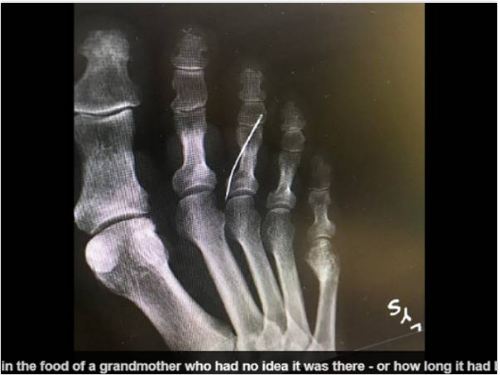

Cụ bà Mỹ bị nhiễm trùng nặng ở chân vì kim khâu đâm xuyên vào ngón chân. Tuy nhiên, bà lại không hay biết gì. Bà bị tiểu đường và căn bệnh đã khiến bà không cảm nhận được cơn đau của những vết thương nhỏ ở chân.

Ảnh chụp X-quang cho thấy kim khâu nằm trong chân cụ bà người Mỹ ẢNH CHỤP MÀN HÌNH DAILY MAIL

Cụ bà chỉ phát hiện mình bị kim đâm khi được chụp X-quang. Bà bị tiểu đường là dường như đã mất cảm giác ở chân, khiến dù bị kim đâm nhưng vẫn không hay biết, theo Daily Mail.

Trường hợp của cụ bà đã được cô cháu gái chia sẻ trên mạng xã hội. Nó như là một câu chuyện cảnh báo về nguy cơ bị tổn thương chân ở bệnh nhân tiểu đường.

Các bác sĩ đang điều trị nhiễm trùng ở ngón chân cho cụ bà. Danh tính của bệnh nhân không được tiết lộ. Bà đang sống ở bang Georgia (Mỹ). Gia đình không biết cây kim đã đâm vào chân bà như thế nào và nó đã nằm ở đó bao lâu.

Cây kim đã được lấy khỏi chân cụ bà sau một ca phẫu thuật khẩn cấp. Sau đó, các bác sĩ tiếp tục điều trị nhiễm tụ cầu khuẩn và hiện bà vẫn đang còn trong bệnh viện.